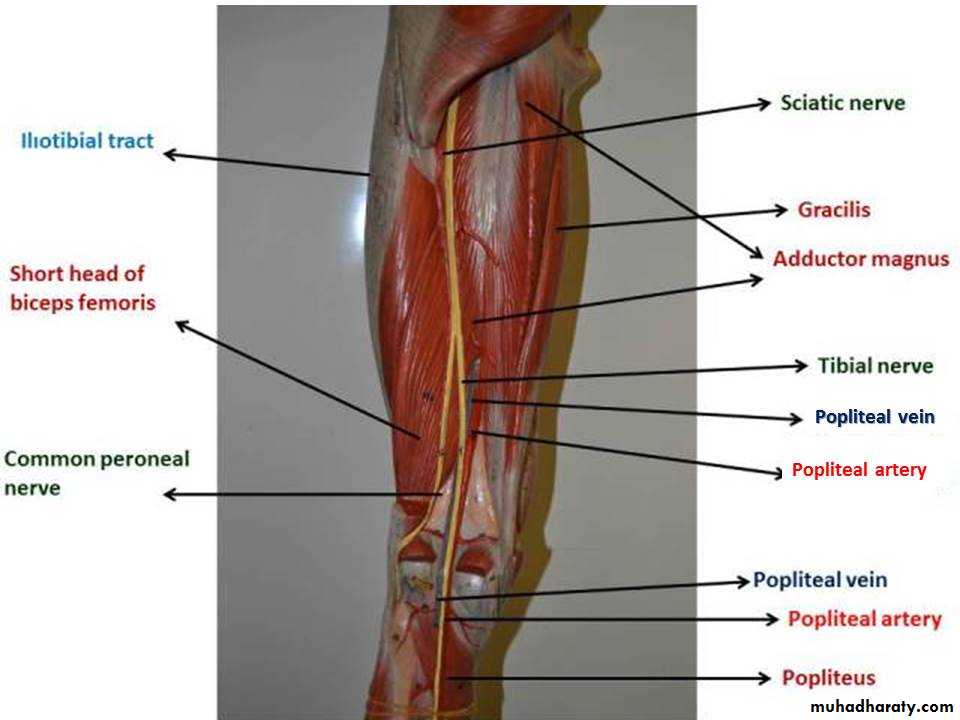

Practical Anatomy of The Lower Limbs for 1st Year Students

Prof.Dr.Abduljabar Alhubaity

Dep.of Anatomy/College of Medicine

University of Mosul